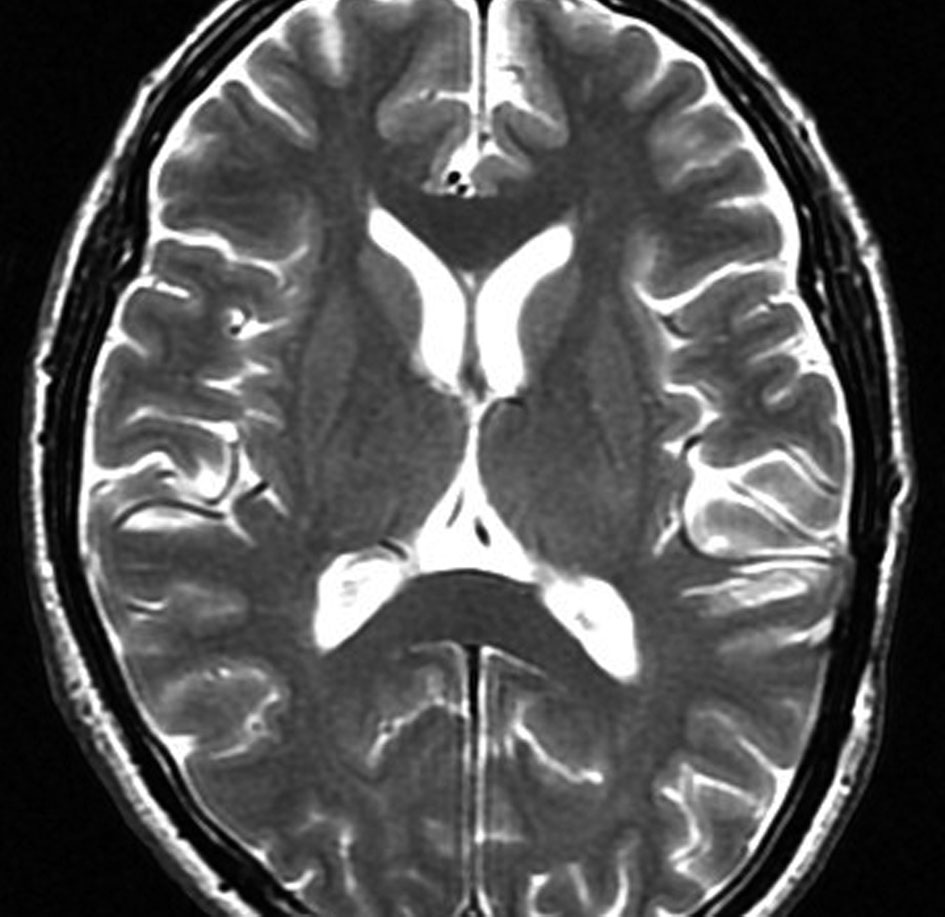

悪性グリオーマと区別しづらい

左はT2強調画像です。内部は壊死にみえますが,転移性脳腫瘍の特徴である周辺脳浮腫がほとんどありません。右のガドリニウム増強では周囲が不規則に造影されます。肺腺癌に特徴的な画像かもしれませんが,膠芽腫との区別が難しく,原発巣もわからず単発ですと生検術が必要になります。FDGでもMet-PETでも脳腫瘍自体は鑑別はできません。FDG-PETで他の臓器に病巣があると転移としていいでしょう。